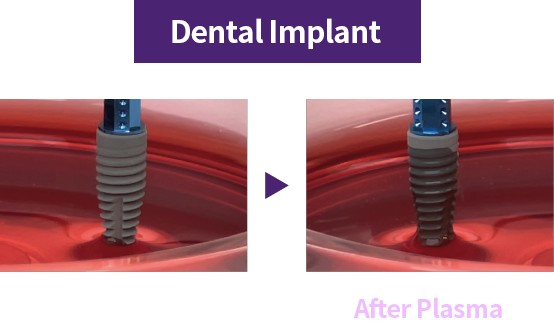

Using plasma technology, these implants remove surface impurities and help achieve excellent biocompatibility, faster bone integration, and shorter recovery time.

During manufacturing, shipping, and long-term storage, hydrocarbons can accumulate on the implant surface, reducing biocompatibility. Plasma implants remove hydrocarbons with high-energy plasma and reactivate the surface for higher biocompatibility.

Plasma cleaning activates the surface → faster bone bonding → shorter recovery

Plasma treatment improves surface hydrophilicity → promotes blood and protein adhesion → an implant the body accepts more easily

Plasma treatment helps remove impurities left on the implant surface and improves surface hydrophilicity for better biocompatibility. Thanks to these benefits, plasma technology helps improve implant success and serves as a key factor for faster recovery.

Creating a safer implant surface through removal of surface impurities

Improved early protein attachment through organic removal and surface activation